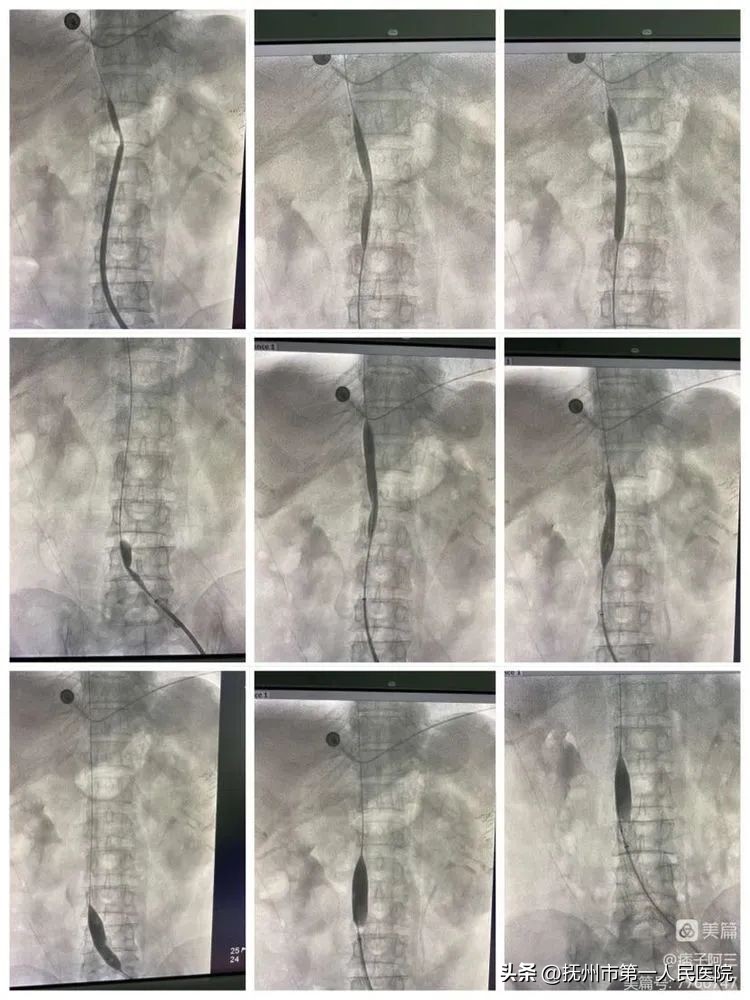

10分钟后再次造影发现、下腔静脉回缩再次狭窄、患者下腔静脉长段闭塞狭窄遂行下腔静脉支架植入

支架植入术中造影

并给予F14球囊内扩